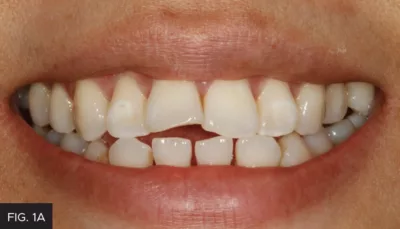

A simple black-and-white photograph of the light-cured composite was taken with a smartphone, which validated the correct value. (FIG. 2)

black and white photo, verify shade of composite

Shade recipes are obtained through the creation of discs on hydrated teeth. The discs are made up of layers of potential shades and opacities of composite. A black and white photograph verifies that the value of the selected composite is a match to the existing dentition.